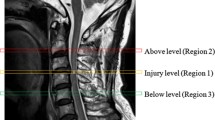

In all available follow-up examinations, tract-specific signal change was evaluated without any clinical information. First, the level of the injury was determined on sagittal T2w. Evaluation of the axial T2w consisted of evaluation for (1) T2w hyperintense signal change in the region of the dorsal column (DC) one level above the level of the injury, (2) T2w hyperintense signal change in the region of the lateral corticospinal tract (CS) one level below the level of the injury, and (3) T2w hyperintense change in the region of the lateral spinothalamic tract (ST) one above the level of the injury. Signal abnormality was read as present or absent. Examples for signal abnormality in each tract are shown in Fig. 2.

Sagittal and axial T2w MRI of the cervical spine of five different patients demonstrating examples of signal intensity change consistent with Wallerian degeneration (WD) in the dorsal column (DC), the lateral corticospinal tract (CS), and the lateral spinothalamic tract (ST). Axial plane is indicated by the blue line on the corresponding sagittal image. a A 19-year-old patient 348 days after motor vehicle accident (MVA) demonstrating WD in the DC on axial images (white arrow). On median, sagittal imaging, WD (white arrows) can be appreciated from the injury upwards to the medulla oblongata. b A 22-year-old patient 109 days after fall demonstrates WD in the DC on axial and median sagittal imaging (white arrows). In the anterior cord, bilateral WD in the ST is seen (black arrowheads). c A 60-year-old patient 111 days after surfing accident also demonstrates WD in the DC (white arrow) and ST (black arrowheads) on axial imaging. On median sagittal imaging, faint WD in the DC is seen (white arrows). d A 50-year-old patient 323 days after MVA demonstrates WD in the CS (white arrows) on axial imaging. On paramedian sagittal imaging, faint WD in the CS from the injury downwards can be appreciated (white arrows). e A 55-year-old patient 216 days after fall demonstrates WD in the CS on axial and paramedian sagittal imaging (white arrows)